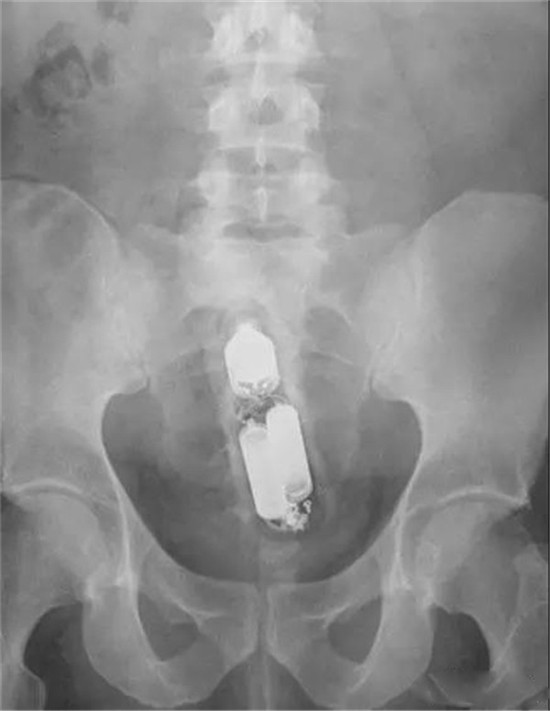

下面我们来看看常见的这些直肠异物。为了保护病人的隐私,X光片已经经过技术处理,看不出任何病人的信息。

这是一个啤酒瓶。男性。

上面是一个啤酒瓶在大肠里。病人是男性。这是常见的肛门内异物。

这种情况,往往只要给病人打上全身麻醉,肛门松弛后,就可以用卵圆钳经过肛门把啤酒瓶拉出来。